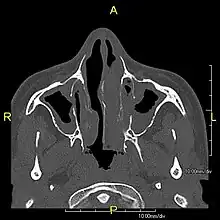

Several diagnostic tests for this condition have been proposed.[5] These include nasal nitric oxide levels as a screening test, light microscopy of biopsies for ciliary beat pattern and frequency and electron microscopic examination of dynein arms, as the definite diagnosis method. Genetic testing has also been proposed but this is difficult given that there are multiple genes involved.[6]